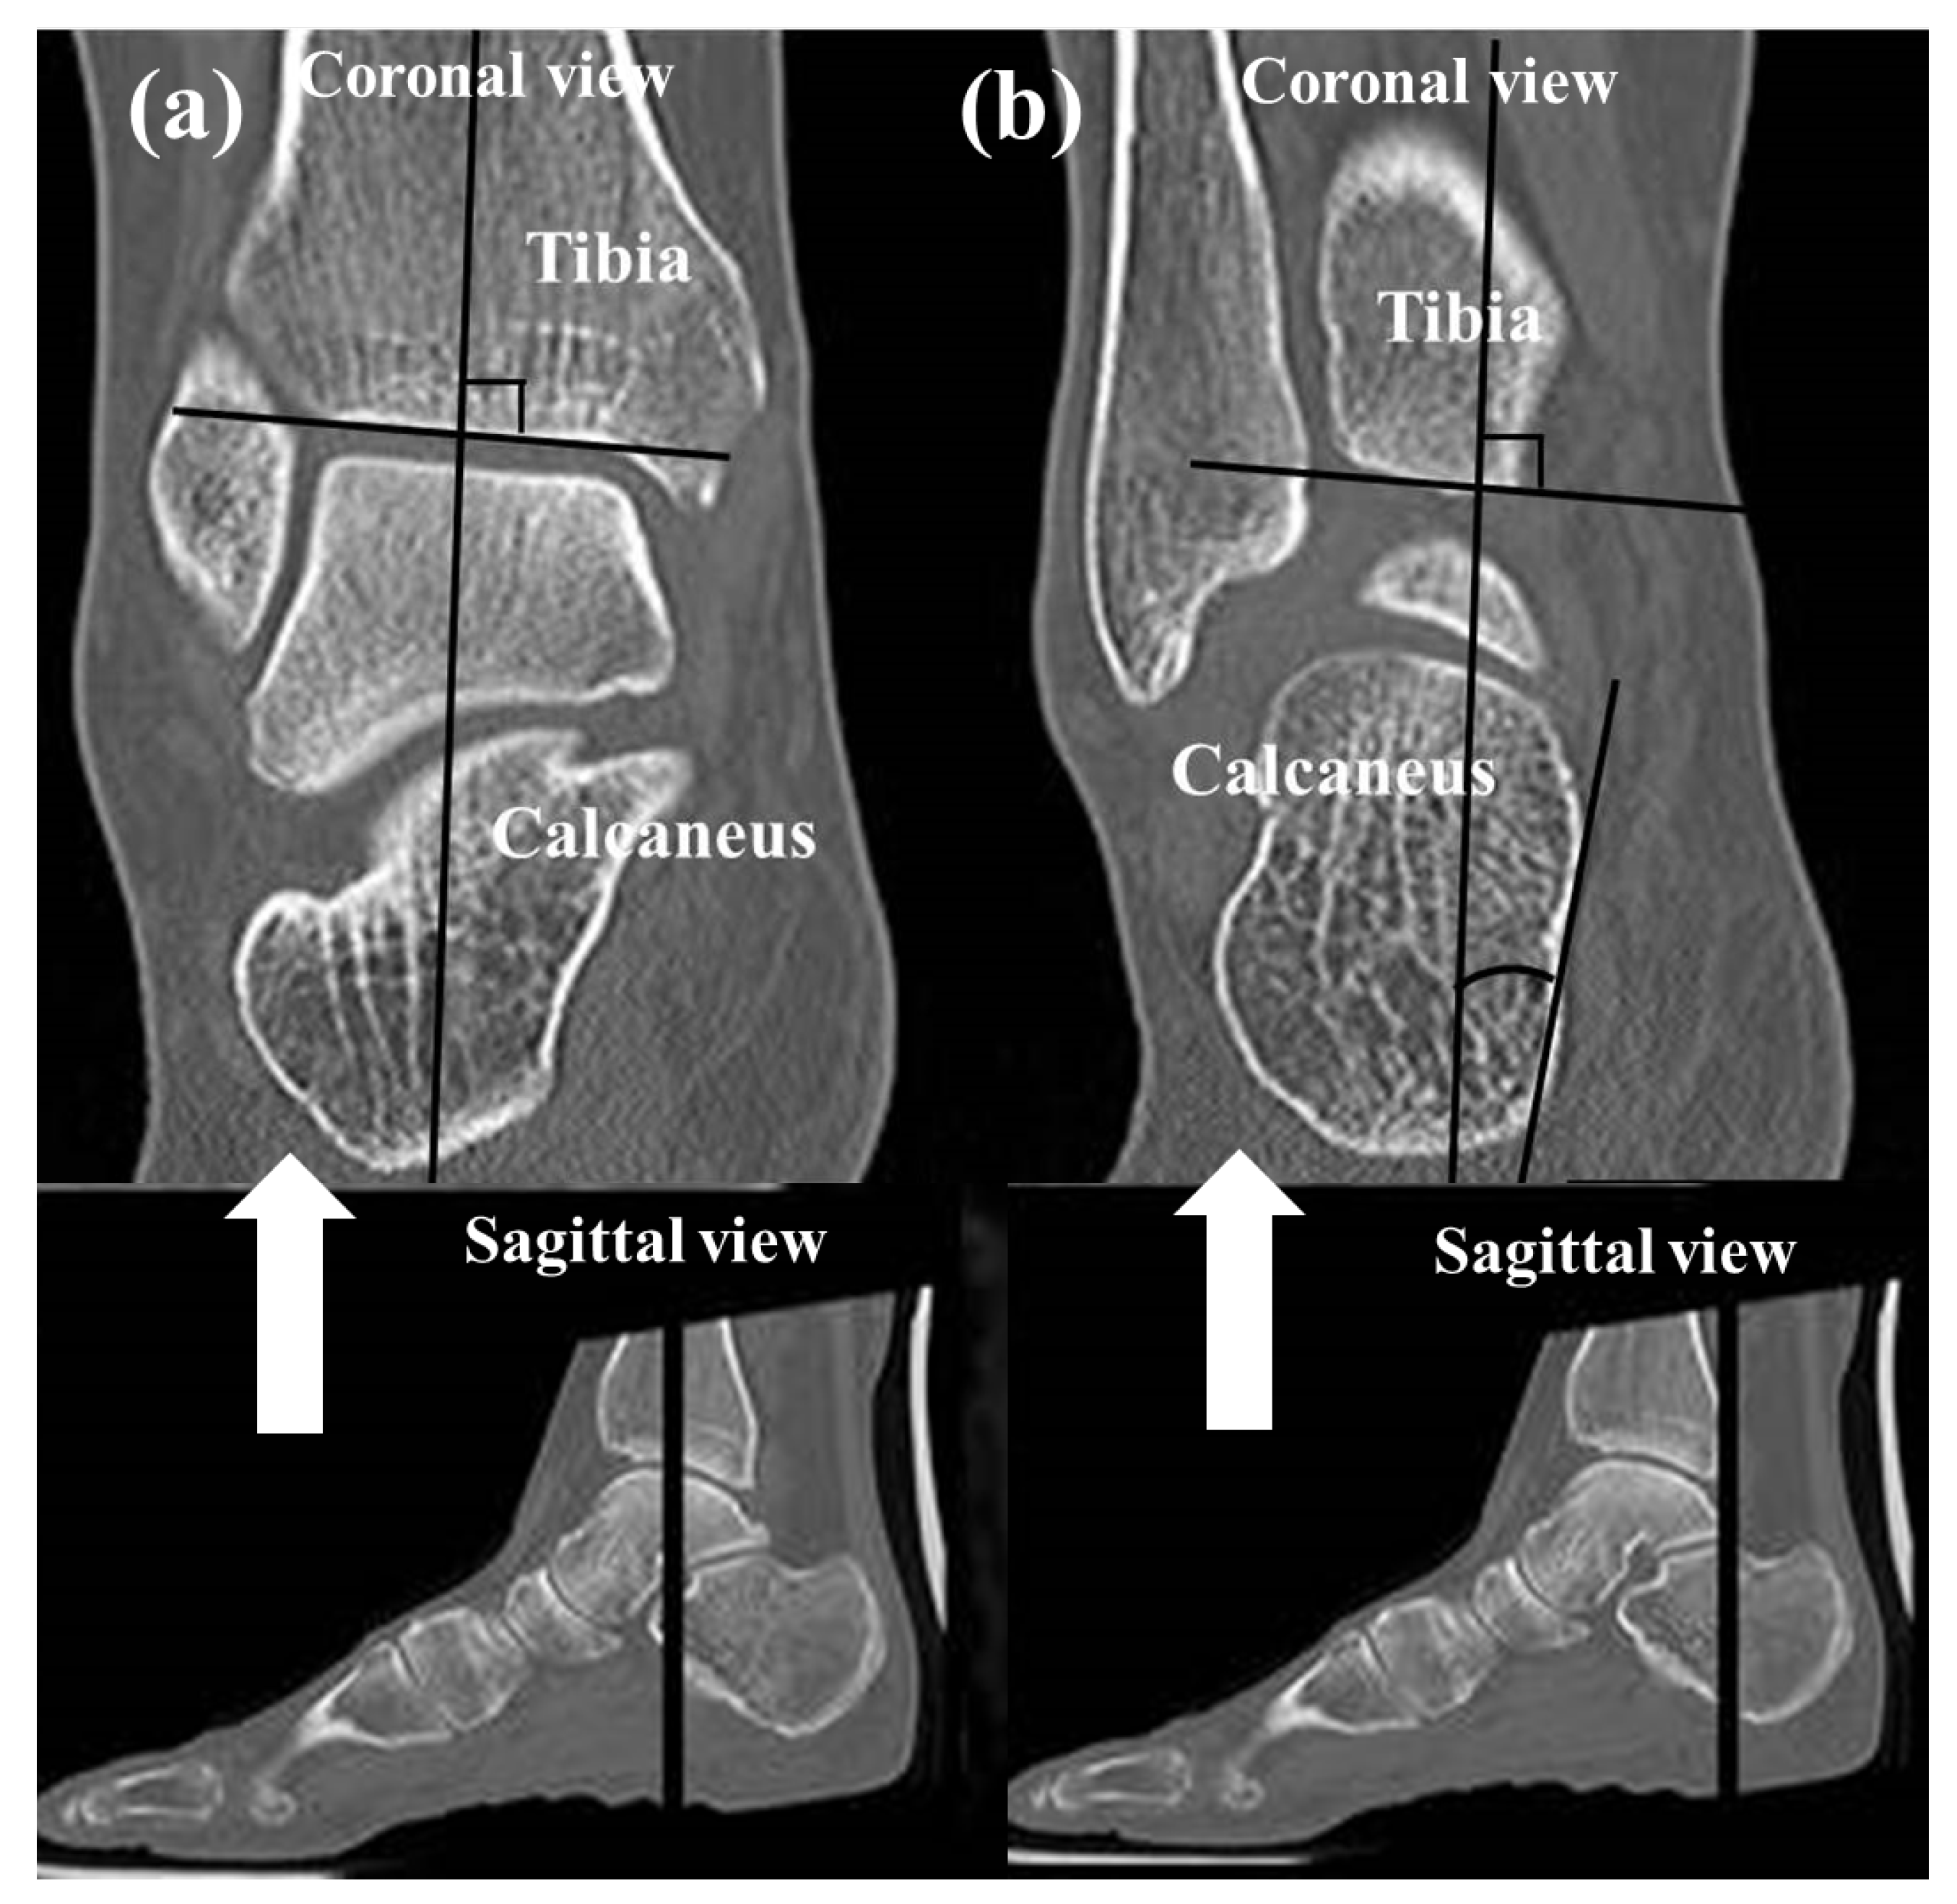

2.4. Subtalar Joint Parameters on CT

To assess the alignment of the hindfoot, including the subtalar joint on CT, four measurements which have been used in previous studies [1,22,23,24,25] were used: (1) the heel valgus angle (HVA), (2) the talocalcaneal distance (TCD) at the Gissane angle, (3) the subtalar joint subluxation (SL) and (4) the calcaneofibular distance (CF). Axial, sagittal and coronal (reconstruction thickness of 2 mm) bone window reformations of axial images were used for measurements. The heel valgus angle (HVA) was based on the axis of the distal tibial defined by a perpendicular line to the distal tibia joint surface and a line parallel the medial osseous contour of the calcaneus on the most posterior image, including the tibia and calcaneus (Figure 3). Axis of the distal tibia was defined using the most central coronal image through the distal tibial shaft. This image was identified as the one in which the tibial shaft diameter was maximal, and the tibial cortex was sharply defined. The talocalcaneal distance (TCD) at the Gissane angle was assessed measuring the shortest distance from the most inferior aspect of lateral talus process to the floor of the calcaneus in the sinus tarsi. This measurement was seen on sagittal images (Figure 4). The subtalar joint subluxation (SL) and the calcaneofibular distance (CF) were measured in the coronal plane at the level of the most posterior aspect of the fibula (Figure 5). The subtalar joint subluxation (SL) was measured from the lateral margin of the calcaneal articular surface to the lateral margin of the talar articular surface. The calcaneofibular distance (CF) was measured from the lateral margin of the calcaneal wall surface to the medial margin of the fibular articular surface.

Figure 3. Coronal images of the ankle joint show the measurement technique for the heel valgus angle. (a) The axis of the distal tibia is defined by a perpendicular line to the midportion of the distal tibial joint surface. (b) Measurement was obtained on the most posterior image including the tibia and calcaneus between the tibial axis and a line adapted to the medial osseous contour of the calcaneus.